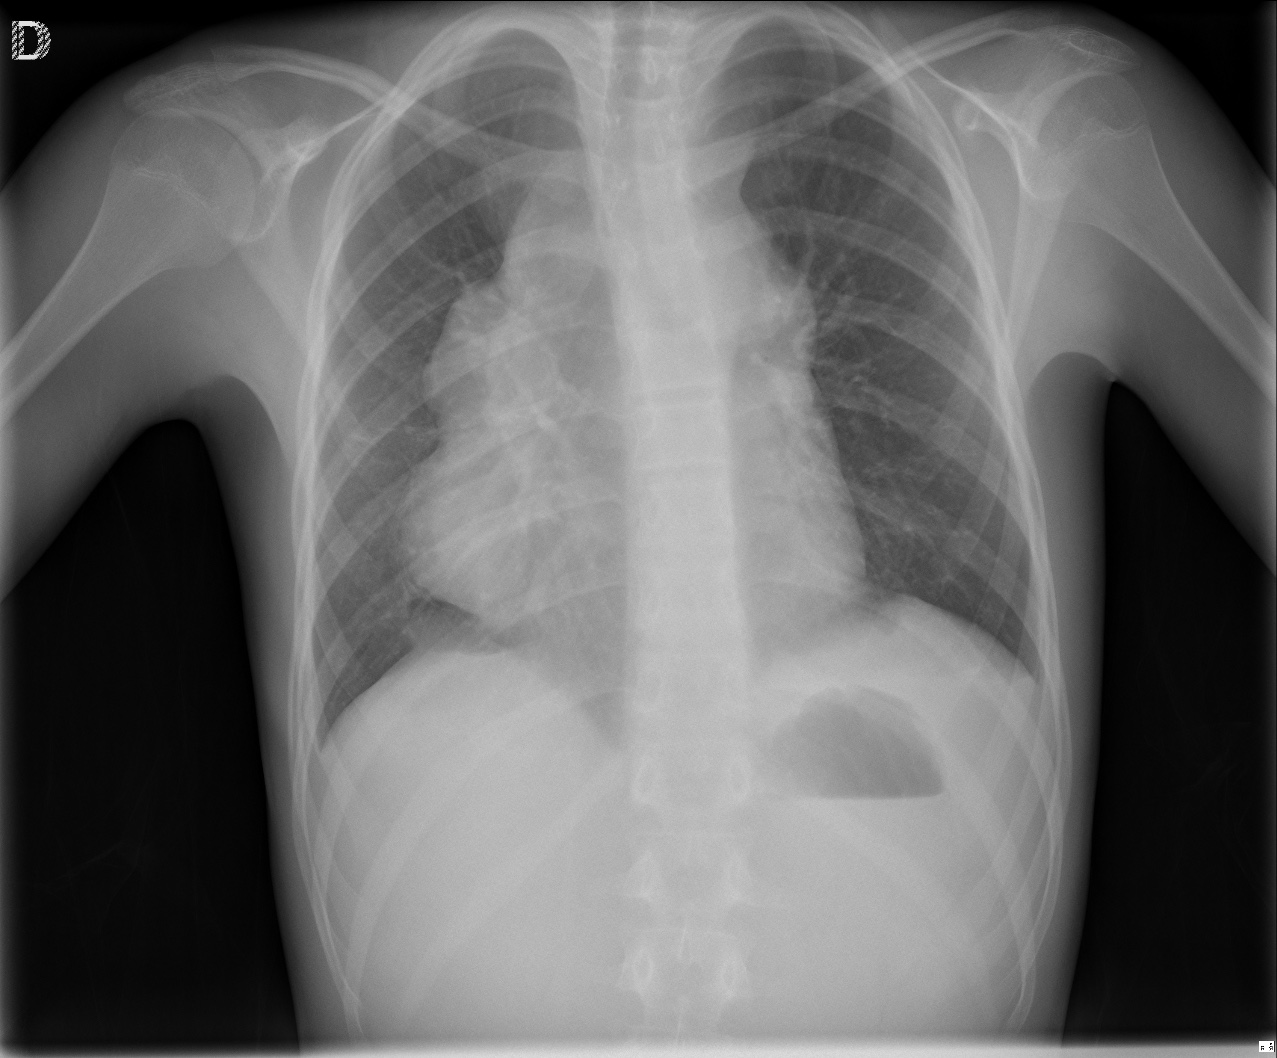

CASO: Niño con sensación disnéica que ha ido incrementado en la última semana.

Hallazgos:

- Se observa un ensanchamiento mediastínico a expensas de una masa que desciende el hemidiafragma y borra el borde derecho del corazón.

- En la placa lateral se observa la posición de la masa en posición anterior.

¿ES UNA MASA MEDIASTÍNICA?

Cuando se observa una masa en la placa de tórax, es posible que se localice en el mediastino. Para saber si es una masa mediastínica aquí tenemos unos objetivos a analizar:

- ¿Es una masa mediastínica?

- ¿Es anterior, media o posterior?

- ¿Es posible definir si tiene grasa, aire o líquido?

1)- Las siguientes características indican que la lesion se origina en el mediastino:

- Al contraio que en el pulmón, una masa mediastínica no contiene broncograma aéreo.

- Los márgenes con el pulmón son obtusos.

- Las líneas mediastínicas estarán interrumpidas.

- Pueden estar asociadas anormalidasdes espinales, costales o esternales.

2)- El mediastino puede dividirse en anterior, medio y posterior (la separación es virtual, no hay tejido ni plano que separe estos tres compartimentos). Esta división nos será util a la hora de realizar los diferentes diagnósticos diferenciales.

- En la placa lateral el compartimento anterior y medio se separa dibujando una línea imaginaria anterior a la tráquea y posterior a la vena cava.

- El compartimento medio y posterior se separan dibujando una línea imaginaria que pasa 1cm posterior al borde anterior de los cuerpos vertebrales.

MEDIASTINO ANTERIOR:

Podemos localizar el timo, tiroides, ganglios linfáticos, aorta ascendente, arteria pumonar, nervio frénico. Lo más frecuente es encontar lesiones que afecten al timo o a nódulos linfáticos

Regla de las 4 T’s.

- Timo

- Teratoma

- Tiroide

- Terrible linfoma.

Signos que definen una masa mediatínica Anterior:

- Desplazamiento de las línea mediastínica anterior

- Obliteración del espacio retroesternal.

- Obliteración de los ángulos cardiofrénicos.

- Signo del hilio oculto.

- Borramiento/aumento de densidad de la aorta ascendente.

Nota: En la obliteración del espacio retroesternal se ve un ensanchamiento mediastínico anterior en la proyección PA, mientras que en la lateral se la obliteración/ocupación del espacio retroesternal. Este signo también puede observarse en personas obesas con ocupación de dicho espacio por grasa.